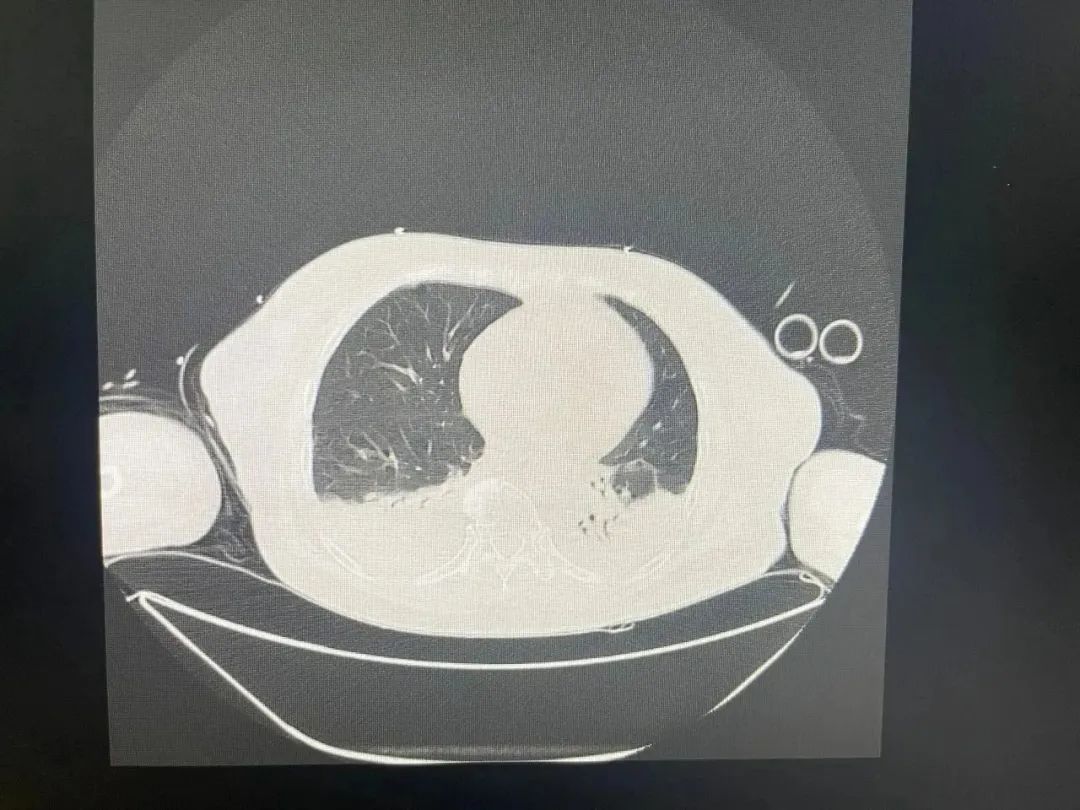

因误吸引发的肺部感染终于爆发

双侧胸腔积液严重

治疗前

11号肺部检查明显好转